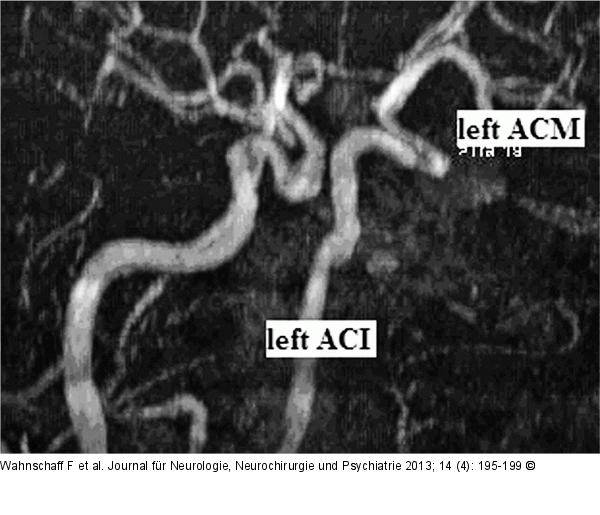

Abbildung 7: Hypophysenadenom Postoperative „Time-of-flight“ (TOF-) Sequenz ohne Hinweis auf eine Stenose der Arteria carotis interna links. |

Postoperative „Time-of-flight“ (TOF-) Sequenz ohne Hinweis auf eine Stenose der Arteria carotis interna links. |